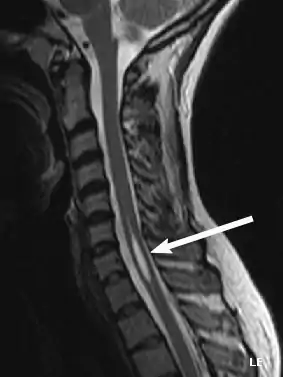

An idiopathic syrinx

Physicians now use magnetic resonance imaging (MRI) to diagnose syringomyelia. The MRI radiographer takes images of body anatomy, such as the brain and spinal cord, in vivid detail. This test will show the syrinx in the spine or any other conditions, such as the presence of a tumor. MRI is safe, painless, and informative and has greatly improved the diagnosis of syringomyelia.[14][15][16][17][18][19][20][21][22][23][24][25]